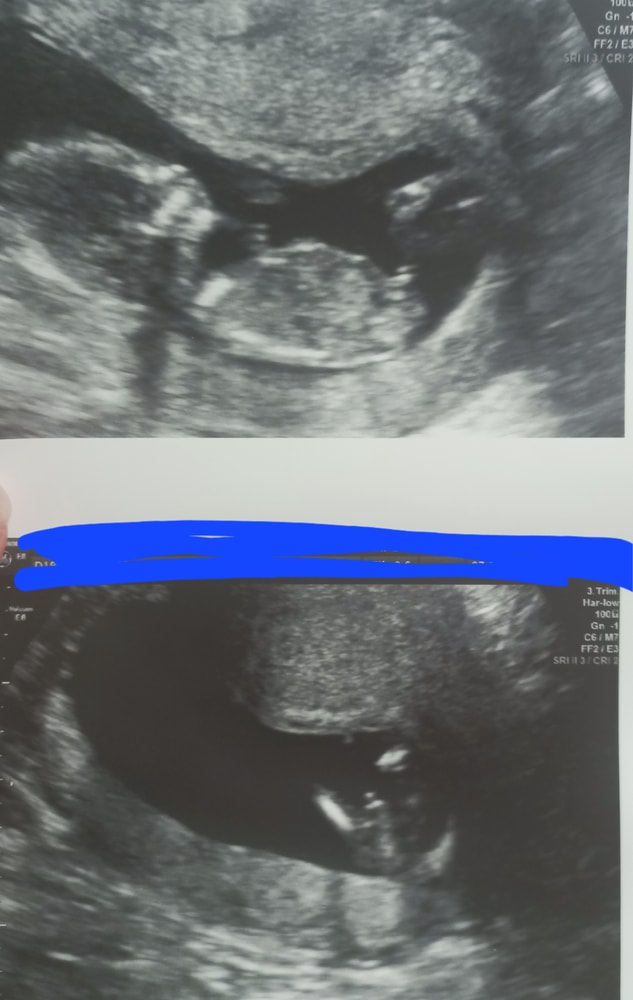

За это время мы поработали аж 2 недели, съездили за 1000км на выходные, нагулялись, вернулись и снова слегли с орви( зато после поездки, а она была на машине в 14 нед, я сходила на узи, а там сын сразу жопкой своей сел и куда мы датчик не поставим, он все энным местом поворачивался, еле дал замеры сделать 😆. Как сказала врач, уже есть ему, чем похвастаться))

Вчера ходила на узи смотреть шейку, заодно проверили СБ, кроха спал) но такой большой) и даже на этих чб экранах он для меня самый сыночка корзиночка сю сю сю🤣🤣🤣